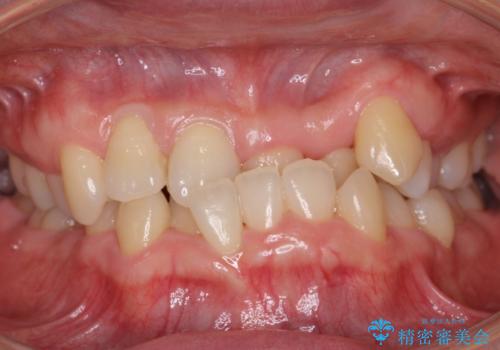

口元を引っ込めたい 前歯のガタガタ

- 前歯のガタガタ、口元の突出感を気にして来院。

歯が出ているせいで口唇が閉じにくく、閉じるとふくれっつらのようになってしまう状態でした。

上下小臼歯を抜歯し、前歯の角度を立てて、位置を後ろに下げました。

前歯をしっかり下げるため、矯正用ミニスクリューを用いました。

口元を劇的に改善することができました。